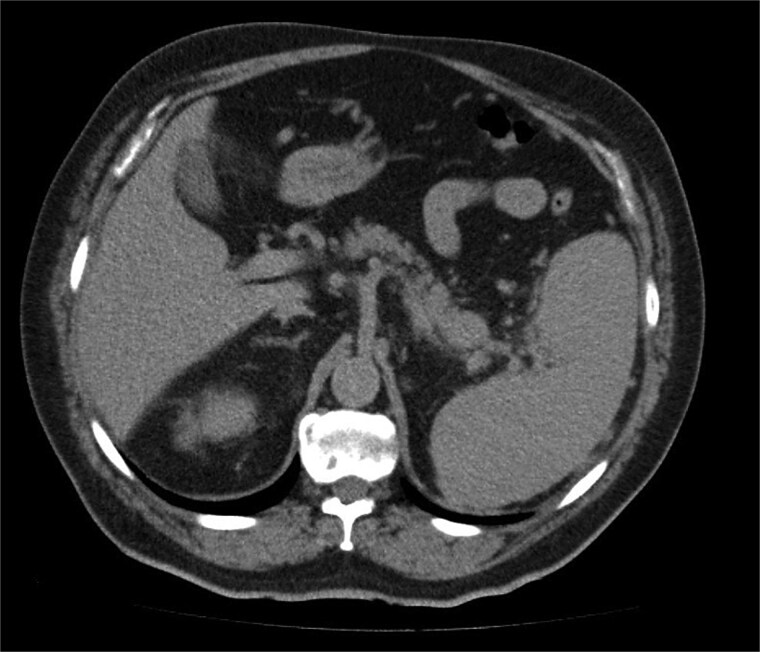

摘要胰腺是肾细胞癌发生远端转移的罕见部位。我们报告一名68岁男性,因肾细胞癌而行左侧根治性肾切除术,术后4年的常规随访影像中发现胰腺尾部有孤立的胰腺转移。患者最初接受帕唑帕尼治疗,但由于胰腺病变进行性生长,无其他转移部位,因此给予立体定向消融体放疗(SABR),在SABR后12个月完全缓解。

The pancreas is a rare site of distant metastasis from renal cell carcinoma. We present the case of a 68-year-old man with a prior history of left radical nephrectomy for renal cell carcinoma, who was found to have an isolated pancreatic metastasis in the pancreatic tail during routine follow-up imaging 4 years postsurgery. The patient was initially managed with pazopanib, but due to progressive growth of the pancreatic lesion without other metastatic sites, stereotactic ablative body radiotherapy (SABR) was given, with complete response at 12 months after SABR.